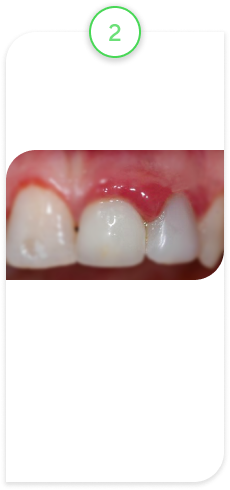

Случай из практики.

Наращивание десны

Пациент обратился с жалобами на оголенный корень зуба, повышенную чувствительность, на неэстетический вид зуба, так как зуб стал выглядеть длиннее, чем раньше.

После обследования поставили диагноз — рецессия десны.

Это патологическое состояние, при котором десна опускается вниз, корень зуба оголяется, появляется чувствительность зуба, эстетический дефект и возрастает риск развития другого патологического состояния — кариеса корня. В свою очередь, кариес корня — это показание к удалению зуба.

В данном клиническом случае провели микрохирургическую операцию по наращиванию десны с применением специального микроскопа. Это дало хороший, долгосрочный прогнозируемый результат.

ВАЖНО! Нужно понимать, что не у каждого оголенного корня можно нарастить десну. Ключевой фактор — стадия, на которой вы обратились. Есть стадии, на которых это невозможно, и единственным вариантом является УДАЛЕНИЕ ЗУБА!

Исходное состояние